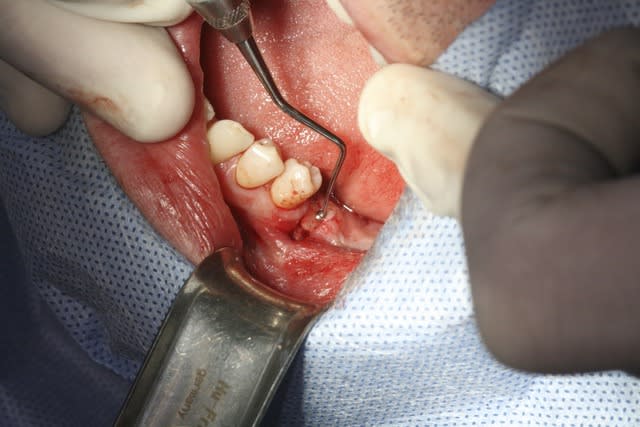

image 2: prélèvement Ramique

image 3 et 4: découpe d'une fine lame allant servir de toit

Désolé pour la qualité, c'est tout ce que j'ai..